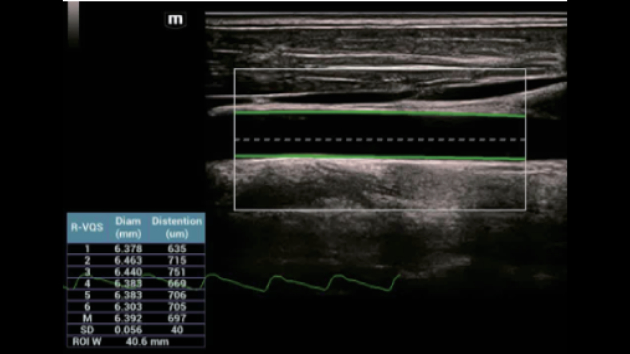

Soluzioni di diagnostica per immagini complete con tecnologia ZST+

La piattaforma ZST+ è un'innovazione straordinaria, che rappresenta un'evoluzione nel campo dell'ecografia. Grazie alla trasformazione delle metriche a ultrasuoni dal beamforming convenzionale all'elaborazione basata sui dati di canale, supera la tradizionale limitazione del trade-off tra risoluzione spaziale, risoluzione temporale e uniformità dei tessuti, offrendo una qualità d'immagine eccezionale per infinite soluzioni di imaging con miglioramenti continui.